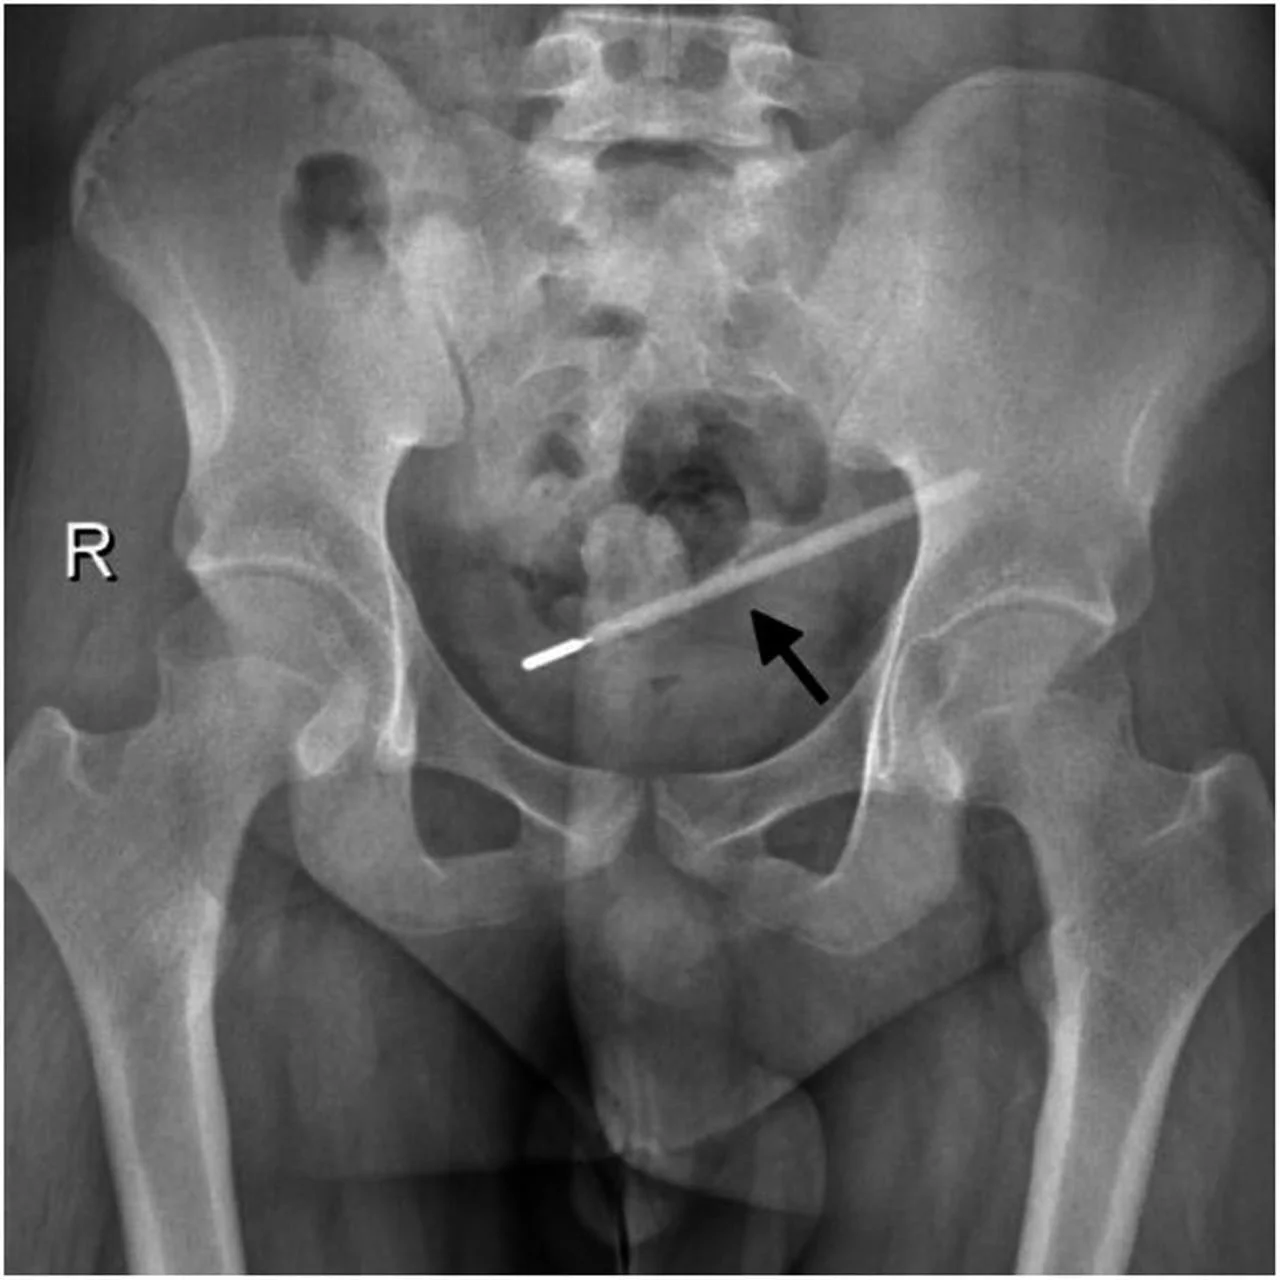

Rendgenska snimka zdjelice prikazuje duguljasti strani predmet označen crnom strelicom.Izvor: Otvoreni izvori

Rendgenski nalaz koji je potvrdio prisutnost živinog toplomjera u abdomenu muškarca nakon 20 godina.